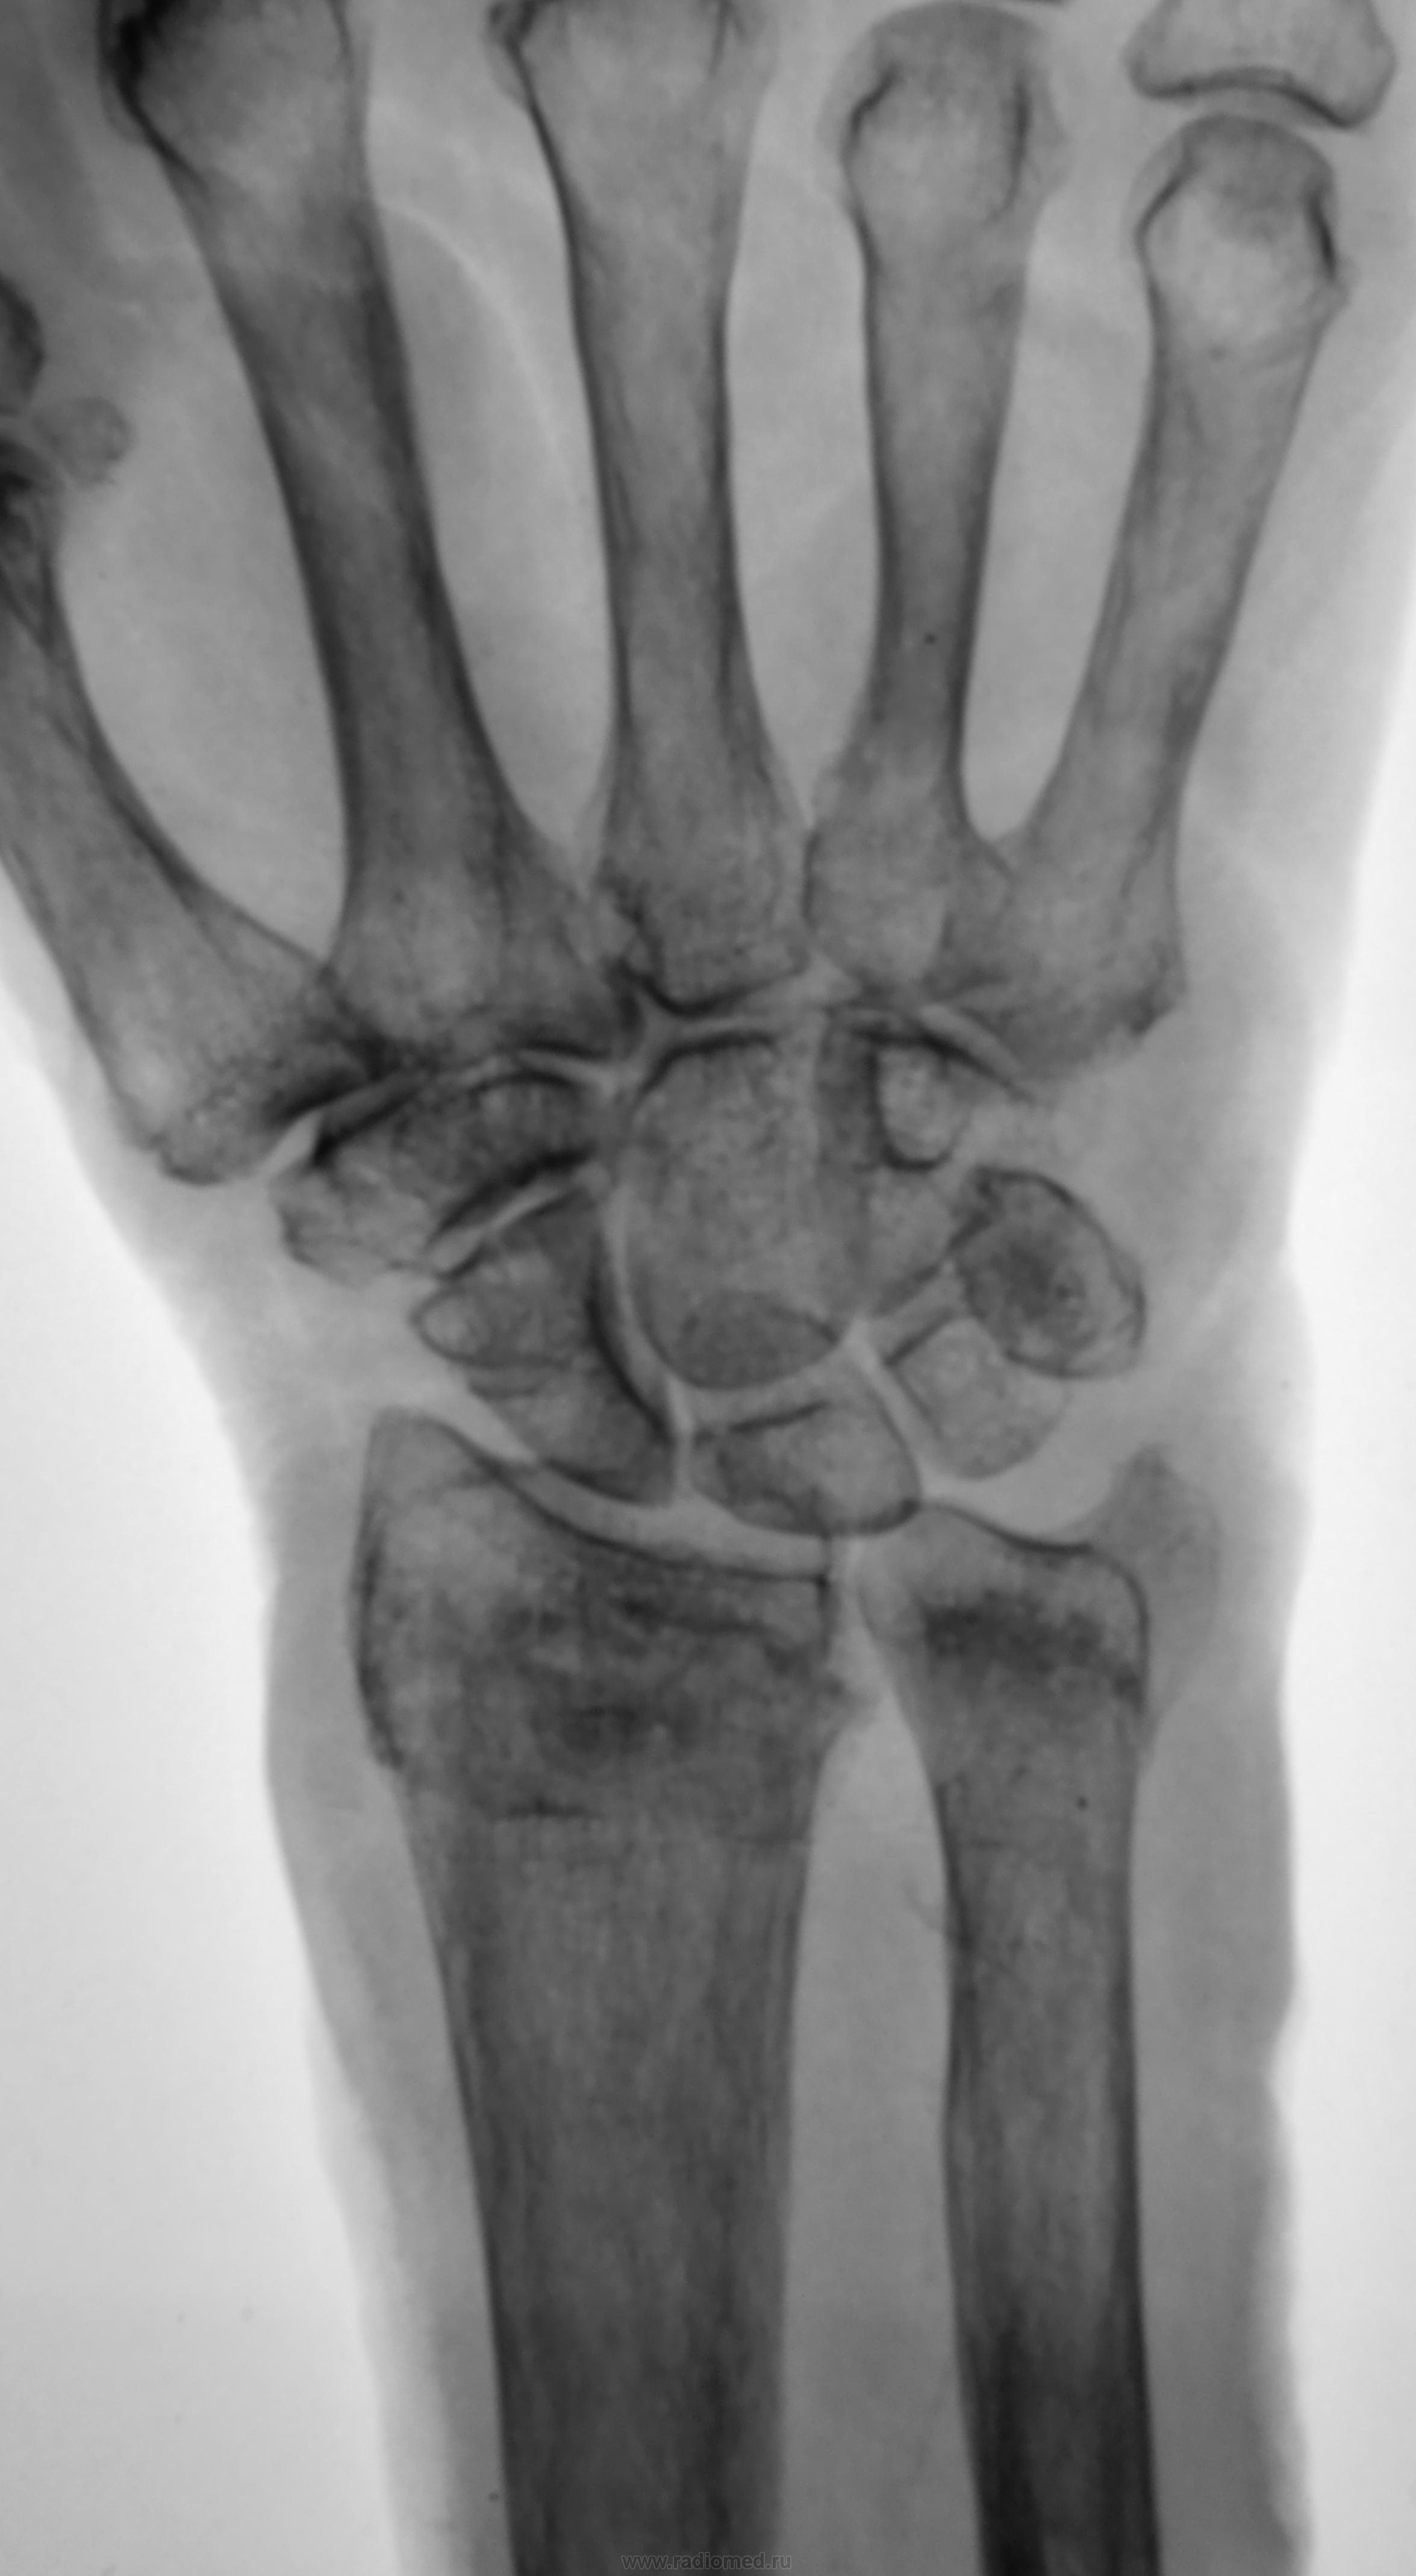

Разгибательная деформация, захождение. Функциональность кисти - тут решит травматолог. Без первичного снимка судить сложно - к примеру, состояние отломков было более удручающим, и в настоящий момент динамика положительная.

Инконгруэнтность в кистевом суставе после репозиции чревата артрозом. Необходимо решать вопрос об оперативном лечении.